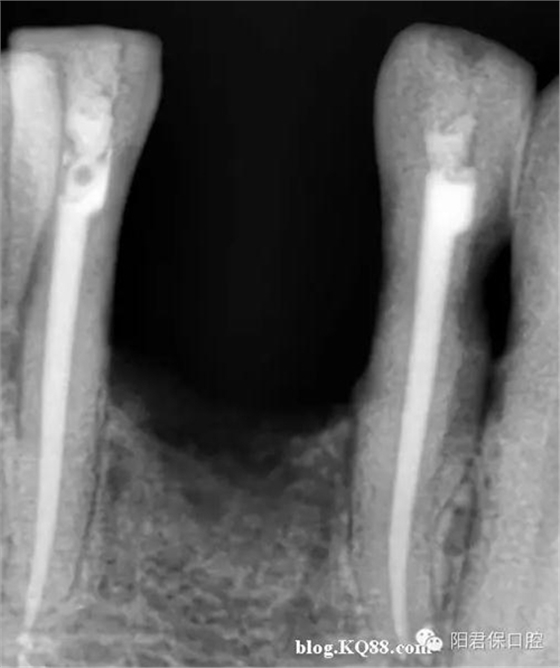

患者:姜XX 性別;女 年齡:65 根據(jù)齲壞程度、患者的癥狀、修復(fù)需要,且對收費及牙髓處理均征得同意后第一次行右下4、5,左下4、5、6;第二次行左下2,右下2 ,右上7一次性根管治療術(shù)。

術(shù)后見右下4,左下4均有側(cè)支充填,且位置對稱,左下6近中根中部有側(cè)支;左下5、左下6遠中根管均多個開口。

熱牙膠垂直加壓后有封閉劑和牙膠超填,但無術(shù)后反應(yīng)。